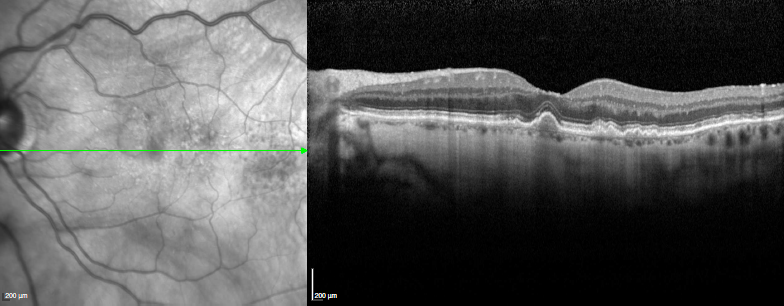

Tomographie par Cohérence Optique - OCT :

pathologie rétinienne et glaucome

Pathologies rétiniennes : DMLA - dégénérescence maculaire liée à l'âge, diabète, myopie forte, occlusion veineuse...